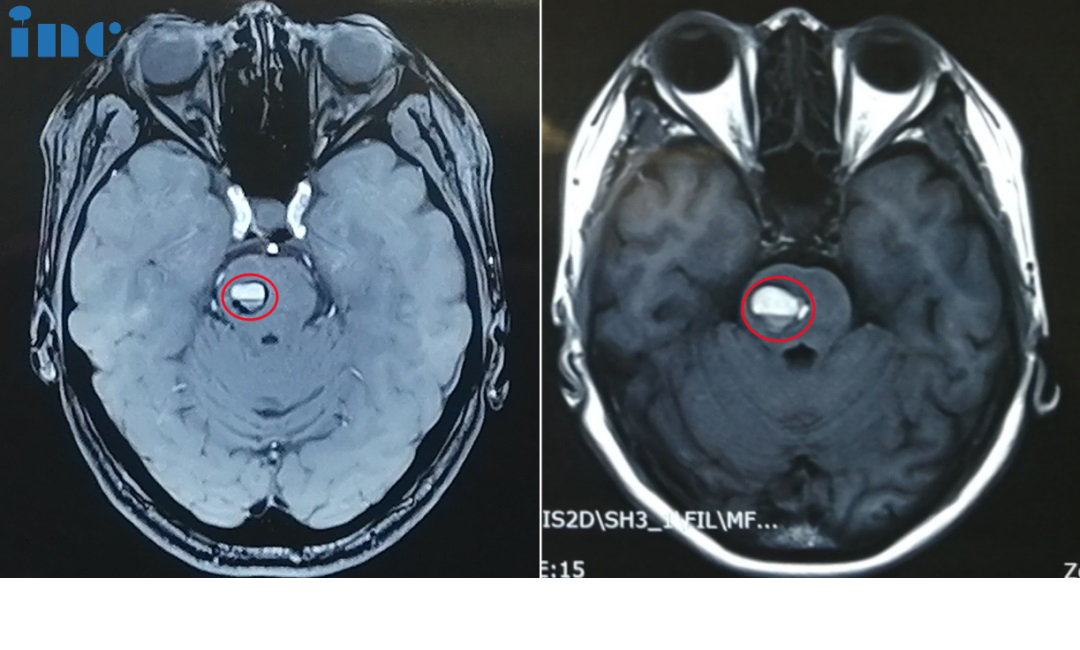

影像对比提示金女士的海绵状血管瘤增大,出血量逐渐增多

术前影像:面神经受压迫

52岁的金女士脑干海绵状血管瘤多次出血,病灶大小两年内迅速增长,出血量一次也一次变大,出血时间间隔也越来越短,导致头晕、眼肌痉挛、耳朵不适等问题,而除了脑干海绵状血管瘤,面神经处的血管分叉形成“剪刀效应”,已经把面神经夹住。因为压迫时间很长,导致了严重的面肌痉挛。

2023年9月28日,巴教授于苏州大学附属独墅湖医院为金女士顺利手术,巴教授成功为金女士取出了这颗脑干位置的不定时炸弹,无任何新发神经功能损伤,同时巴教授也成功进行了面神经解压术,解决了金女士面肌痉挛的问题。